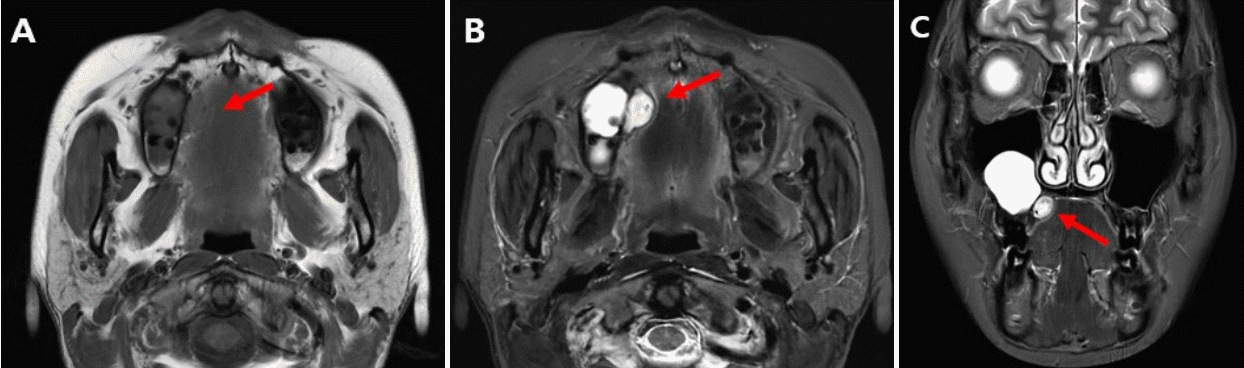

Fig. 2.

Pre-operation magnetic resonance images (MRI). A. Axial T1-weight image showing a well-circumscribed mass on the right side of the palate (red arrow). B and C. Axial, coronal T2-weighted image showing hyperintensity and flow-like void inside the mass (red arrows).